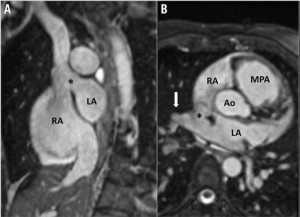

疾患としては図の通り上大静脈下端付近に欠損孔が存在し、後方に存在する左心房との交通を認めます。経過は二次孔欠損型とほぼ同様ですが、洞不全症候群や上室性頻脈の割合が高いなどの特徴があります。病態的な治療適応は二次孔欠損型と同様で右心負荷や血栓症既往などが挙げられます。一方、形態的にはカテーテル治療の適応は慎重な判断が必要です。右房の後方にある右肺静脈部や右肺静脈―左心房接合部付近が、欠損孔になることがほとんどであるため、ステント留置後の右肺静脈圧排、閉塞に注意が必要です。当施設ではMRIによる血行動態評価、経食道エコー、造影CTによる形態評価を行い、さらにCT画像を元に3Dプリンターで疾患モデルを作成し3次元的にステント留置が可能かを評価しています(図2, 図3)。